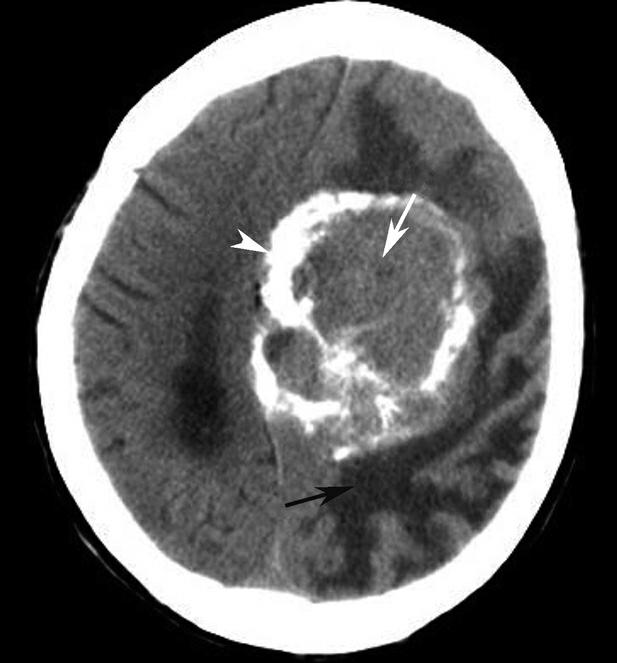

蝶鞍两侧为海绵窦,其内包含颈内动脉及第Ⅲ~Ⅵ对脑神经。海绵窦的密度升高或体积增大常提示病变存在。海绵窦外侧为颞叶,两者之间隔以海绵窦外侧壁。鞍背后方为桥前池及其后方的脑桥,桥前池内可见基底动脉断面,呈圆形稍高密度影。层面中部两侧为颞骨乳突部,其内气化的骨性腔隙为乳突气房。脑桥后方为第四脑室,呈半圆形或新月形,小脑半球的病变(如肿瘤、炎症、出血等)常压迫第四脑室,导致其变形甚至闭塞(图1-2-13)。两侧小脑半球间为小脑蚓部。小脑半球与颞骨乳突部间可见乙状窦。小脑蚓部后方为直窦与上矢状窦汇入窦汇处,窦汇两侧为横窦。静脉窦血栓时可见上述静脉窦增宽、密度明显升高(图1-2-14)。

图1-2-13 第四脑室变形(小脑转移瘤)

A.第四脑室受压变形右移(白箭),提示左侧小脑半球病变;B.左侧小脑半球环形强化结节(黑箭),为瘤体,其周围伴有低密度水肿区